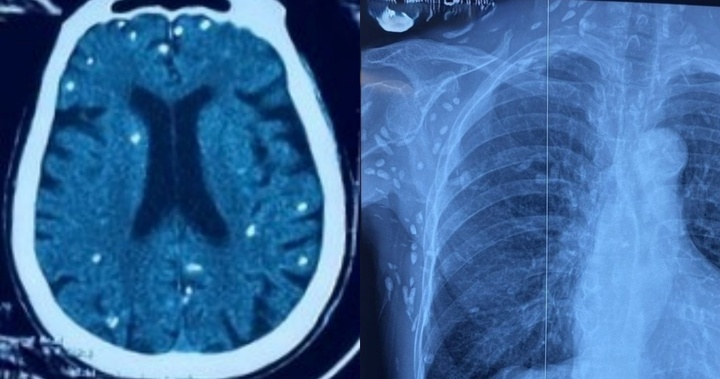

Một người phụ nữ 76 tuổi phải nhập viện do phát hiện hàng trăm nốt sán dây lợn ký sinh ở cả não bộ và mô dưới da.